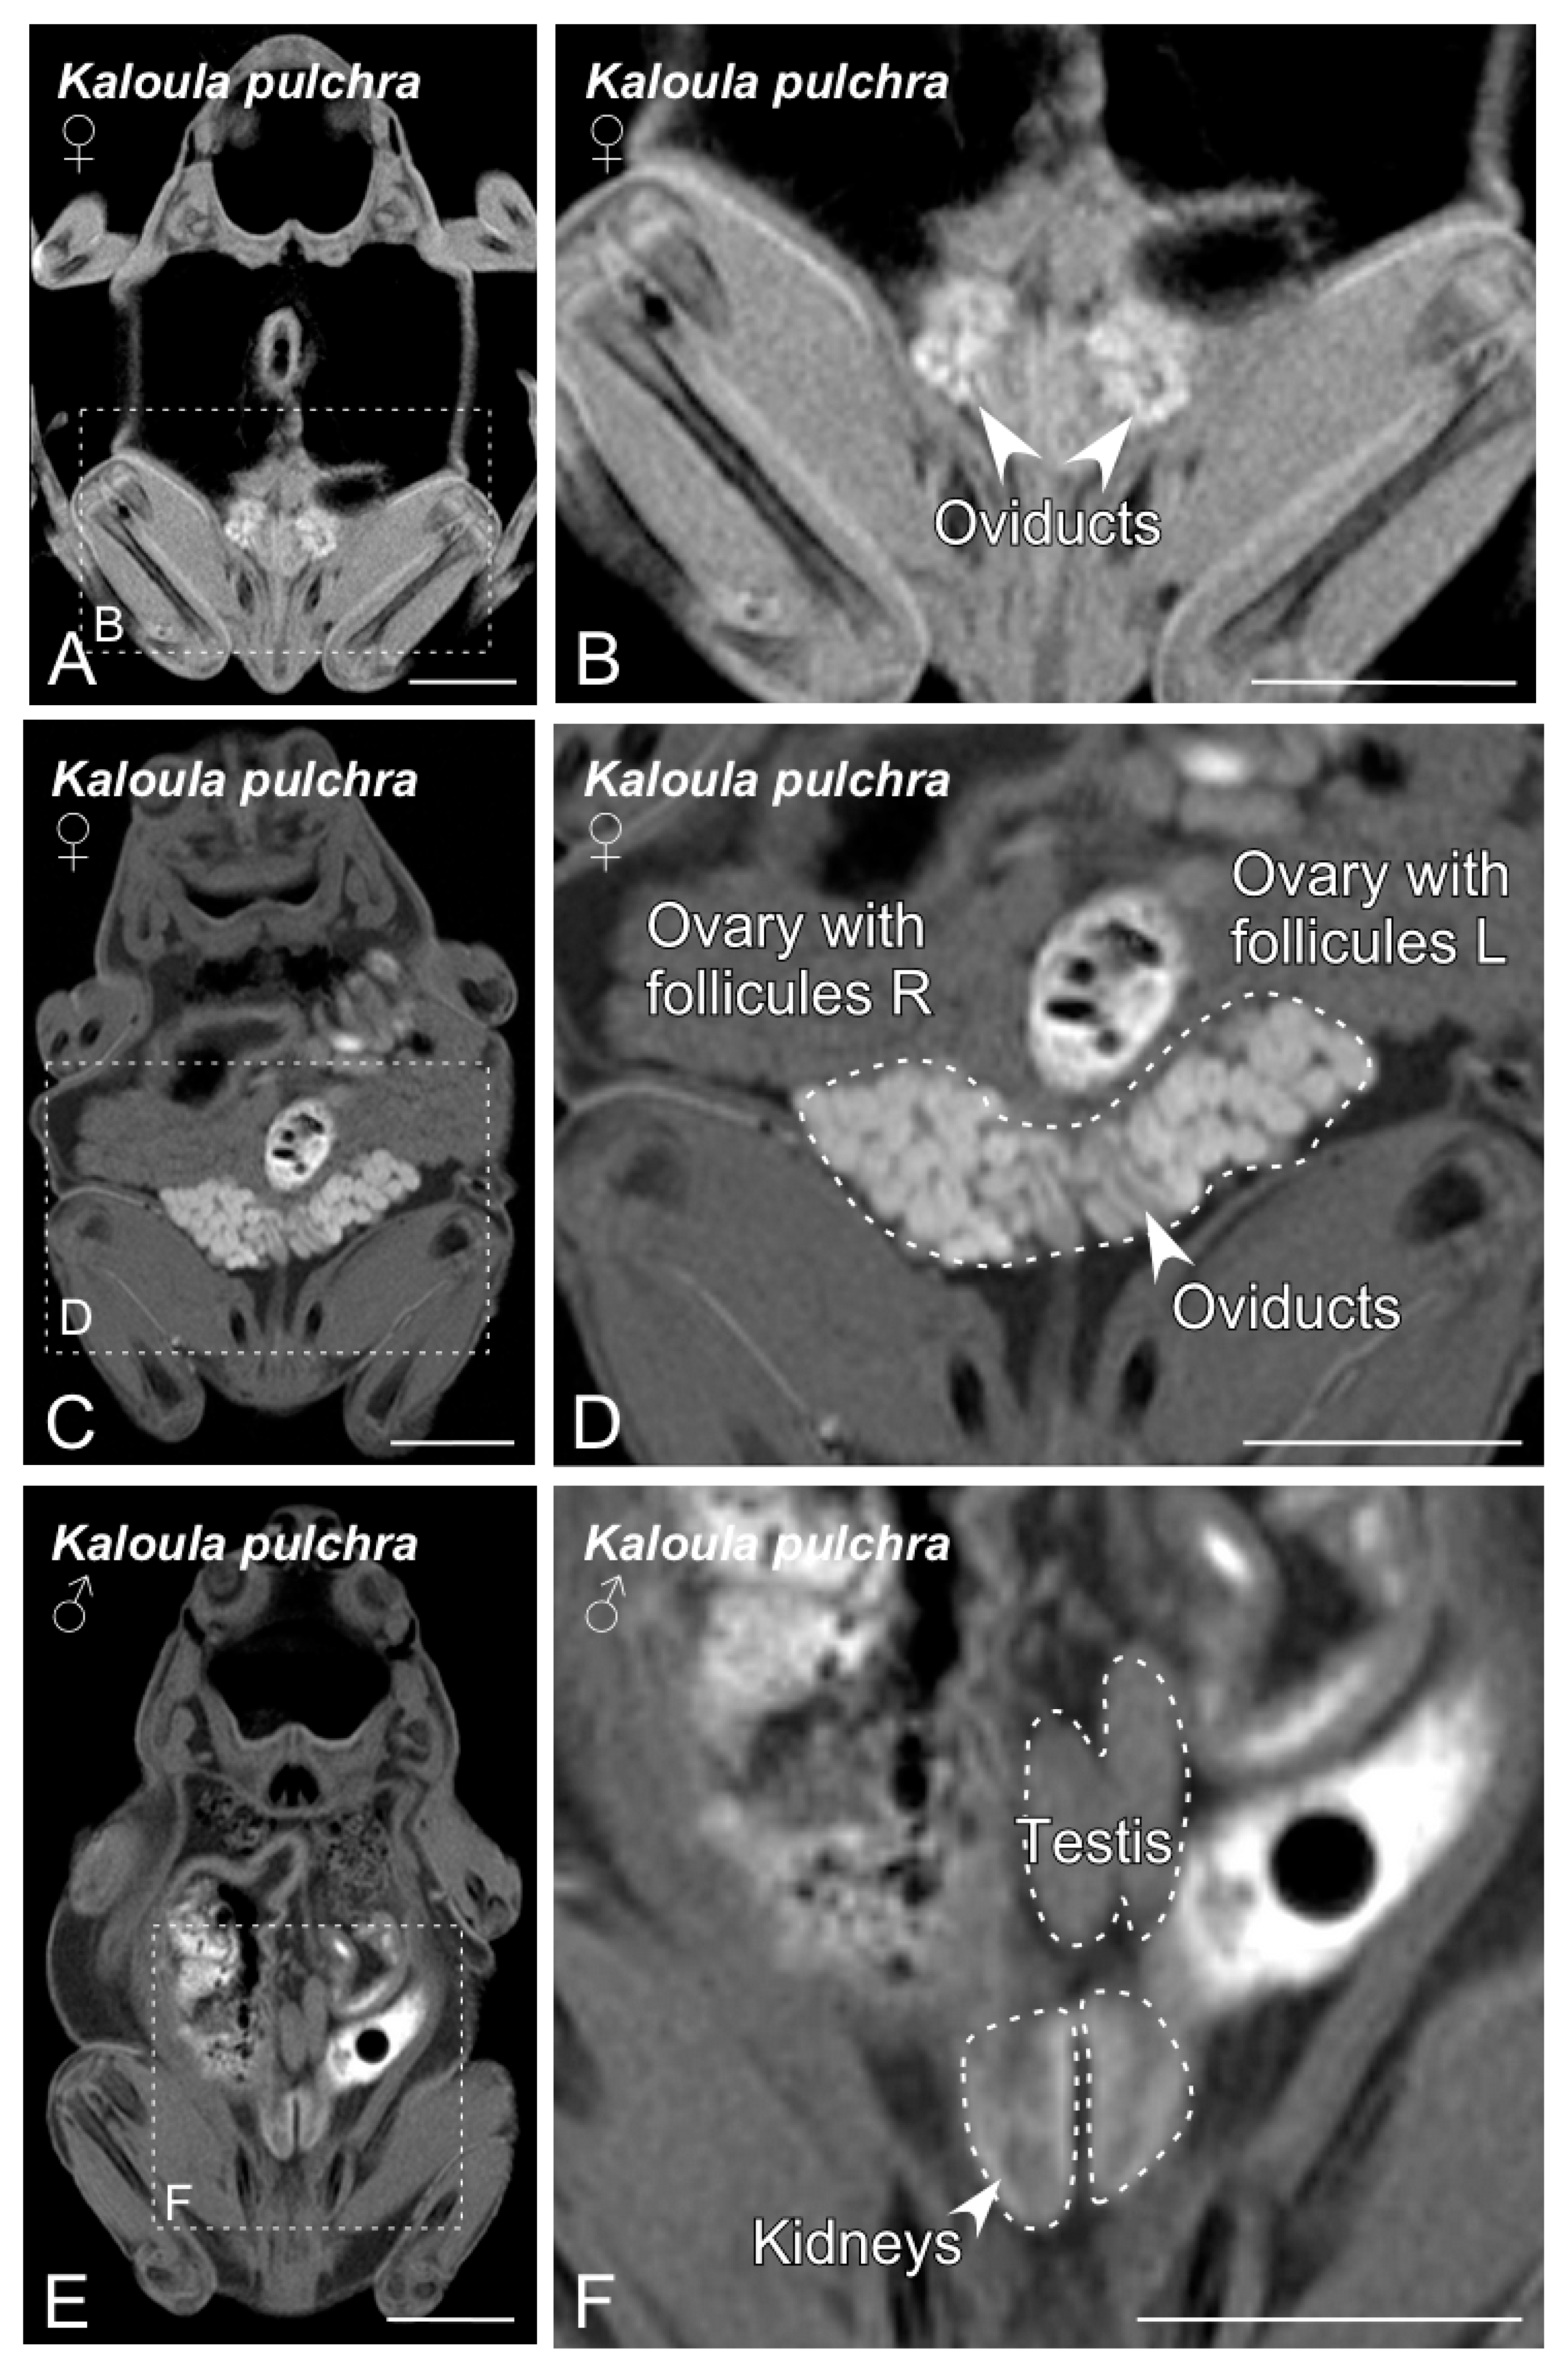

3.1. BT-MRI